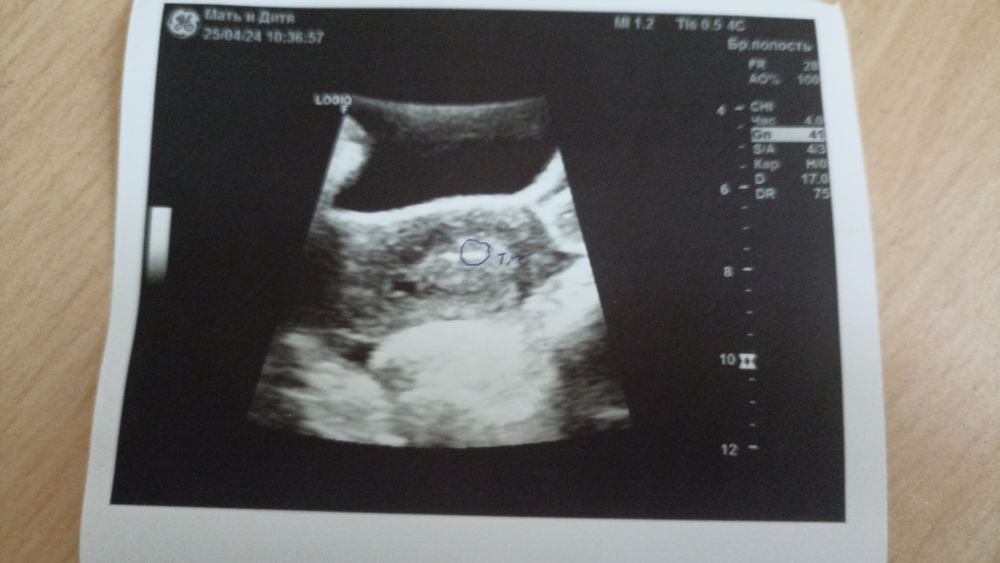

Всём снова здравствуйте) сегодня был день ХУ, утром подсадили эмбриончик 3АА, не знаю как реагировать, рада конечно, представляю что нас уже трое, а котик четвёртый член семьи) Никогда не думала, что забеременею смотря в незнакомый потолок, а туда мне будут заглядывать посторонние люди с прожектором, чудно))) надеюсь, что всё получится и в этот раз мы с моей бусинкой не расстанемся,дажн есть фотка Прописали на след утро укол декапептила и 2р в день утрожестан.